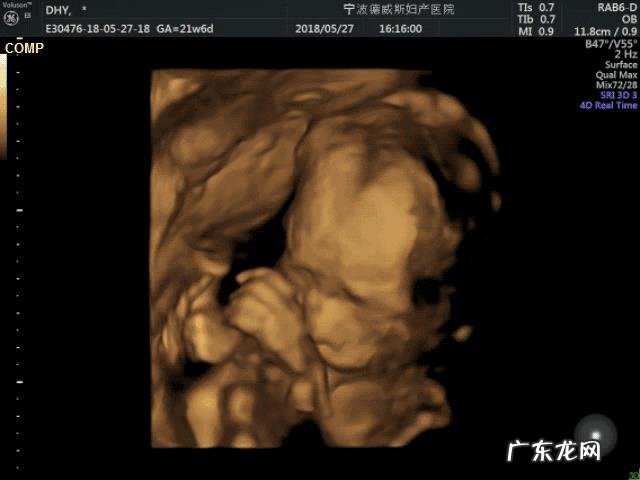

文章插图

四维彩超是应用超声波的原理来显像的,不像X线CT等是靠放射线来成像的,是没有辐射的 。所以说,对胎儿几乎是没有影响的,但是彩超仍然需要有节制的检查,而不是越多越好 。